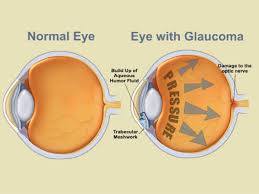

Do you offer laser vision correction?Yes, we provide consultations for LASIK and other laser vision correction procedures. Our experts work closely with trusted surgeons to ensure safe and precise outcomes.What options are available for treating dry eyes?We offer customized treatments, including lubricating drops, prescription medicines, and advanced solutions such as punctal plugs or light therapy for long-term relief.Can I get my glasses on the same day?In most cases, yes. Our in-house optical center can prepare your prescription glasses on the same day or within 24 hours, depending on lens type and availability.Do you provide treatment for glaucoma and cataracts?Yes, we specialize in diagnosing and managing glaucoma, cataracts, and other eye diseases. Our team ensures timely treatment plans and advanced surgical options when needed.Are contact lenses suitable for children and teenagers?Absolutely. With proper guidance and care, contact lenses can be safely worn by children aged 10 and above. Our specialists help select lenses best suited for young eyes.